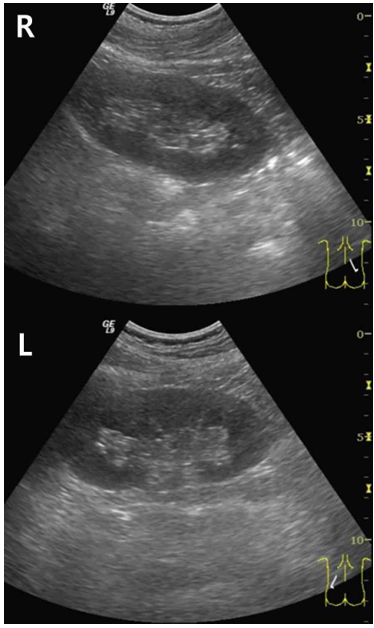

28세 남자가 혈압이 높고 소변검사에서 이상이 있다고 했다며 병원에 왔다. 1년 전에 받은 건강검진에서 혈압은 정상이었다고 한다. 혈압 146/90 mmHg, 맥박 65회/분, 호흡 17회/분, 체온 36.5℃이다. 검사 결과는 다음과 같다. 신장 초음파 사진이다. 진단은?

US: No renal mass, no definite kidney atrophy, normal corticomedullary differentiation